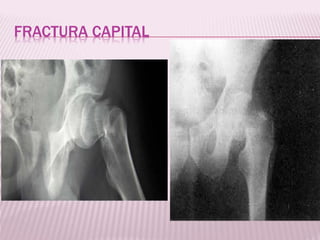

FRACTURA CAPITAL

 Aquellas comprendidas en la zona articular

de la cabeza femoral.

Se produce por

mecanismos de

trauma de baja

energía

Tipo I: Fractura por debajo del

ligamento redondo.

Tipo II: Fractura por encima del

Compromiso de zona de apoyo

Tipo III: I y II con fractura del

cuello femoral.

Tipo IV: cualquiera de las

anteriores mas fractura del

acetábulo,

Clasificación de

Pipkin